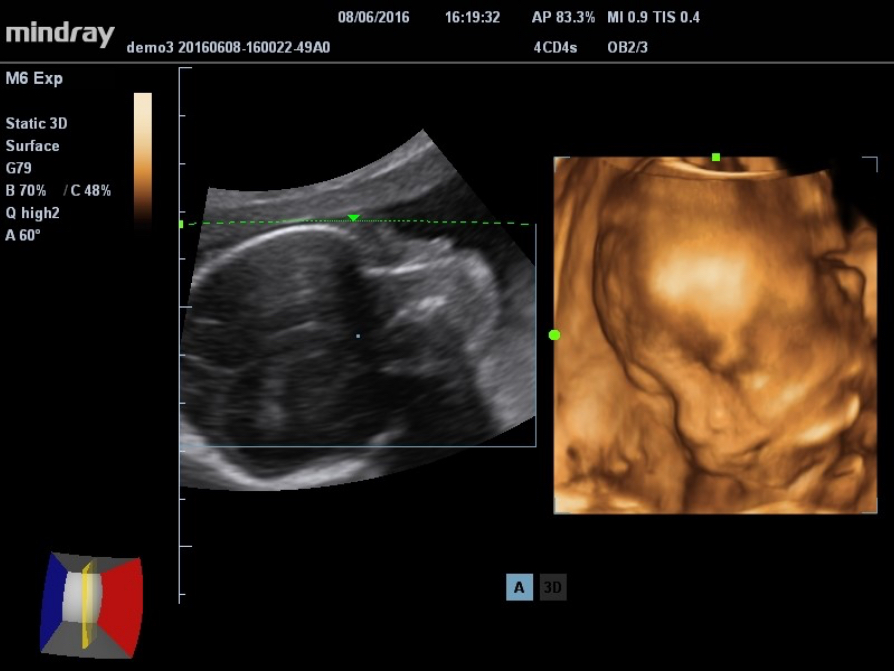

3D/4D imaging technology delivers a range of tools that help take advantage of the full value of volume data. With rich rendering modes, more information on fetus structure is made available to make a more confident diagnosis.